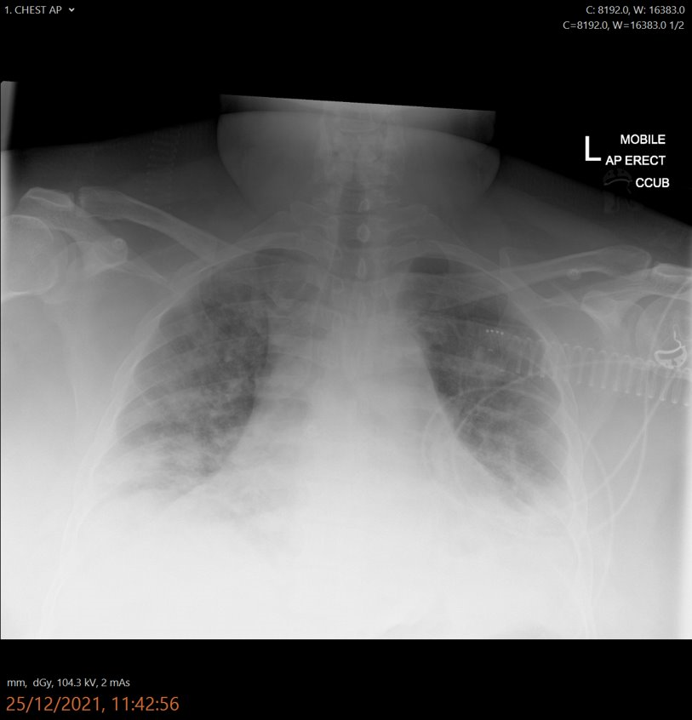

Critical care patient. Known covid. ?status of chest

• Bilateral consolidation (1)

• Pleural effusions / cardio-megaly (1)

• Relating to covid (1)